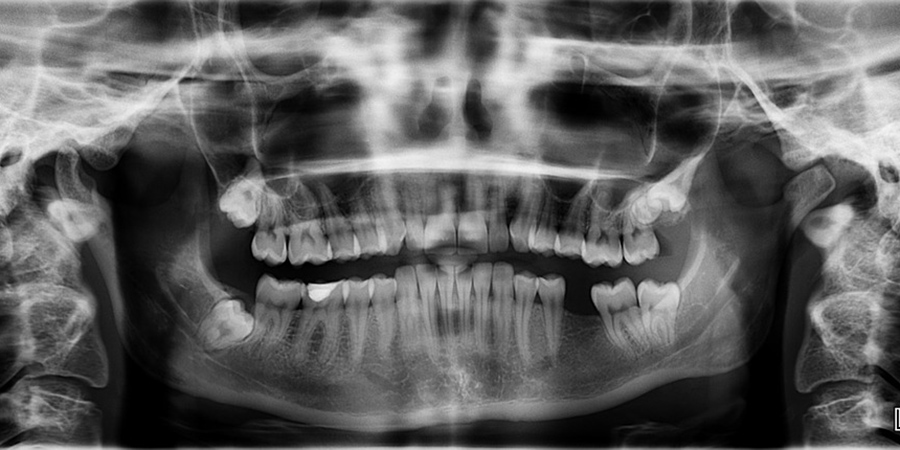

В России медицинским организациям больше не требуется лицензии на выполнение работ (услуг) по рентгенологии. Как сообщает территориальный орган Росздравнадзора по Саратовской области, такой приказ Минздрава РФ вступил в силу со вчерашнего дня, 28 марта.

Согласно документу, речь идет о выполнении рентгенологических исследований в различных стоматологических и ортодонтических кабинетах не только в медицинских организациях, но и в образовательных, в призывных пунктах, на предприятиях. Теперь лицензия не нужна на применение дентального рентгеновского аппарата с цифровым приемником изображения (радиовизиограф).